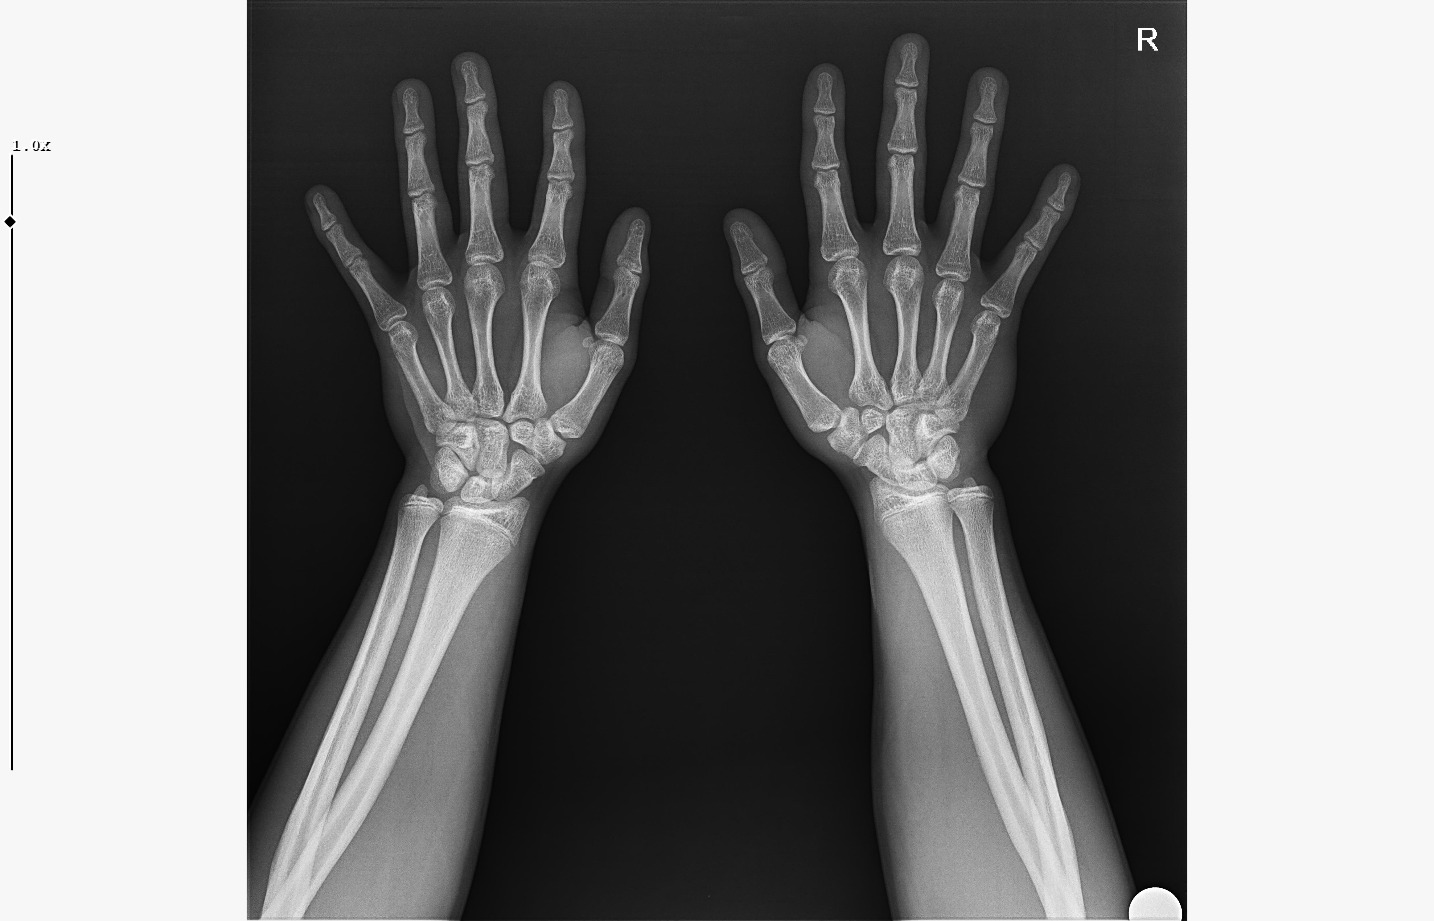

doktor bi sik bilmiyodur büyük ihtimalle plakları buraya at biz bakak

röntgeni atar mısın?

• WhatsApp Image 2026-01-07 at 00.31.08 (1).jpeg

WhatsApp Image 2026-01-07 at 00.31.08 (1).jpeg

140.5 KB · Views: 0

bilmiyo zaten,ki el plakları boy ile neredeyse hicbirsey göstermiyo bile ama tr de hangi doktora gidersen git %95inden fazlası el plağına bakcak ona göre yorum yapcak

bilmiyorum nasıl eğitim alıyorlar da ya eskimiş yada mantık kurma yetenekleri yok

kemik yaşın 15 gibi 15'e çok yakın

anne baba boyun ve yaşını bilmiyorum sadece bu bilgilerle 171-175 arası diye tahmin ediyorum röntgen ile.

normalde anne babana göre 171-176 olman gerek zaten. kemik yaşın ve şuanki boyun ile yapılacak tahmin anne baban ile yapılabilecek tahminle nerdeyse birebir aynı yani büyük ihtimal o civarlar olursun bence